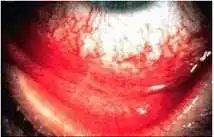

(如图)睑腺炎的诊治中,以下哪些是正确的()

A.内睑腺炎的切口应该与睑缘平行

C.积极应用抗生素眼液,控制感染

D.应局部冷敷,利于止痛

E.脓肿形成后,要尽快挤压排脓,利于消肿